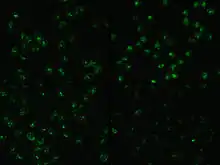

Immunofluorescence

Immunofluorescence is performed by the production of anti-antibodies with a fluorescent molecule attached, making it a chemiluminescent molecule, which provides a glow when subject to ultraviolet light.[13] Antibodies are added to a bacterial solution, providing an antigen for the binding of fluorescent anti-antibody adherence.